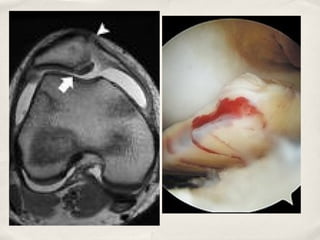

OCD

✤   Factors associated with failure of non-op treatment

✤      Larger sized lesion

✤      Greater Skeletal maturity

✤      High signal behind lesion on MRI

✤   Treatment

✤   Operative

✤      Anterograde or retrograde drilling

✤      Lesion Stabilisation

✤      Microfracture

✤      Cartilage "replacement"

✤           OATS/Mosaicplasty/Autologous

chondrocyte transplantation